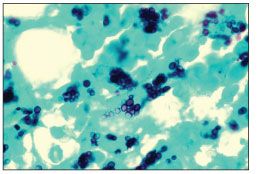

The peripheral blood smear obtained on admission showed reactive neutrophilia with toxic granulation, rouleaux formation, and intracellular yeast forms consistent with Histoplasma capsulatum (Figure 1). Peripheral blood cultures yielded growth of H capsulatum. With a CD4+ cell count of 4/µL, the patient was given a diagnosis of AIDS. A chest radiograph showed a right lower lobe infiltrate, and sputum cultures were positive for M tuberculosis and negative for fungal organisms.

Figure 1.Peripheral blood smear showing reactive neutrophilia with toxic granulation, rouleaux formation, and intracellular yeast forms consistent with Histoplasma capsulatum (hematoxylin-eosin, original magnification ×100). (Illustration courtesy of the department of hematology-pathology at the Keck School of Medicine at the University of Southern California.)